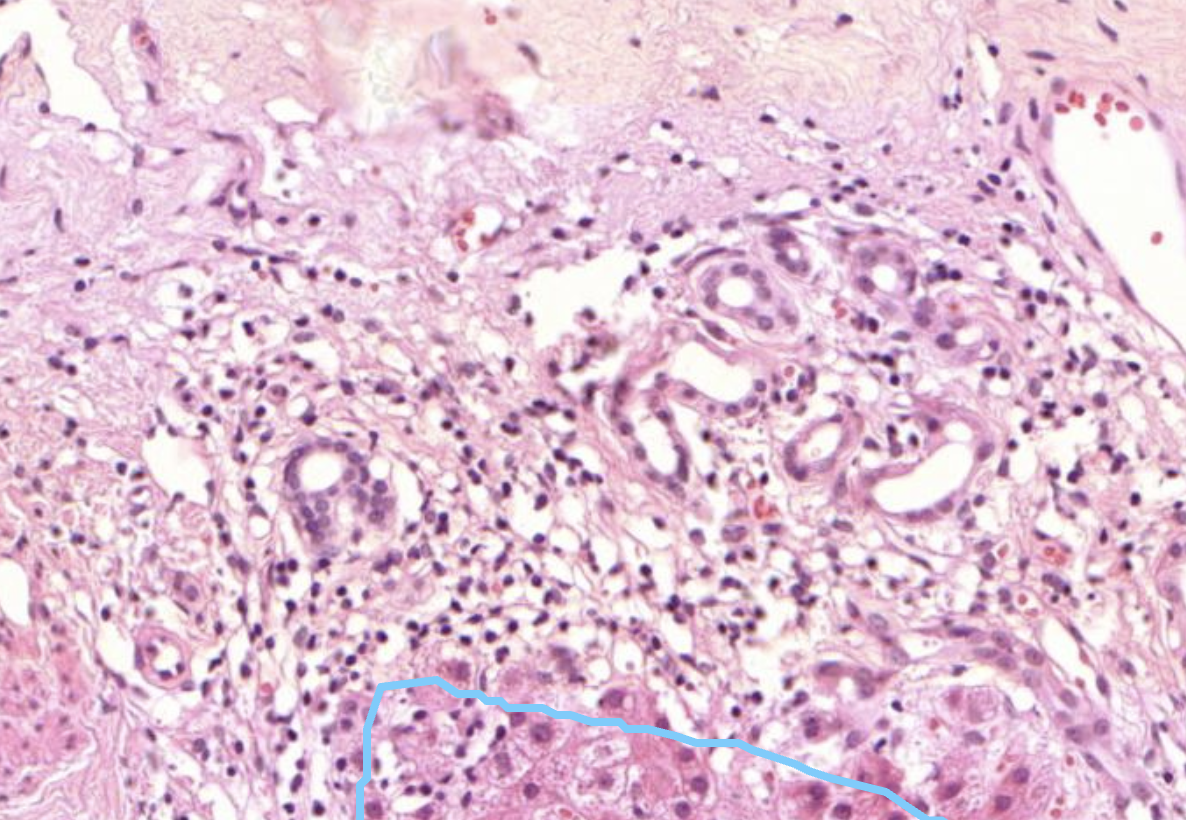

40) Was sieht man hier im Mittelpuntt?

Histopathologisches Bild: Kolonschleimhaut

Es zeigt sich Lymphatisches Gewebe der Colonschleimhaut, sogenannte Pleyer Plaques.

40) Was ist hier links zu sehen?

Colonkarzinom. Links sieht es recht unordentlich aus. Es zeigen sich in kleinen pools auch leukozyten und Fibrin. Hier sind auch super viele Zellen zu sehen .